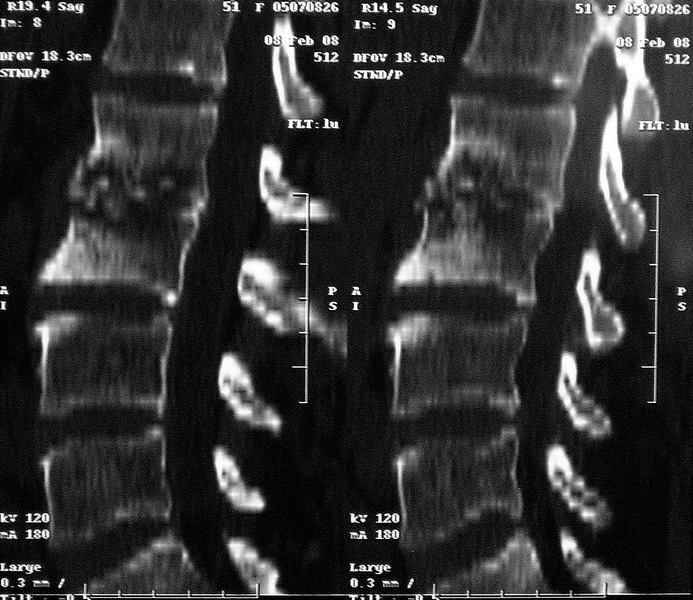

Отправляю MRI в динамике, снятые с пленки на фотоаппарат.

|

По данным представленных КТ и МРТ у больной имеется достаточно выраженная степень деструкции тел позвонков (около 30% общей костной массы тела позвонка), что определяет высокий риск возникновения патогических переломов и появления локальной кифотической деформации на этом уровне.

Судя по снимкам похоже идет речь о спинальном остеомиелите для диф диагноза стоит провести черезкожную пункционную биопсию(с помощью КТ)